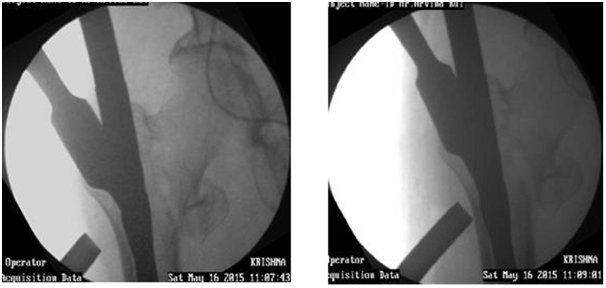

Before distal locking

1. Chance to correct rotational deformity.

2. Palpate patella hidden under drapes.

3. Release traction. Impact if fracture transverse.

4. Do not impact if comminuted.

5. Drill far cortex well as otherwise bolt may not progress. Specially in midshaft with thick cortex.

6. If drill hits on nail switch to smaller drill bit or thick K wire. May use smaller bolt or cortex screw.

7. Check length of bolt in Carm before final tightening of bolt, as changing of bolt is tedious (Figure 33). Tying Vicryl to bolt is an option.

Figure 33 Before distal locking.